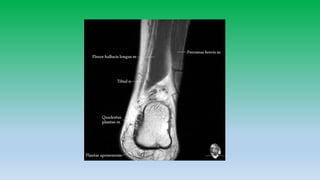

Posterior ankle tendons:

• Achilles and plantaris tendons are located in midline of posterior ankle and is

largest tendon in the body, diffusely low in signal intensity. Usually has flat or

concave anterior margin on axial images. Becomes convex when diffusely

thickened. Normally tendon measures 7 mm in AP-diameter.

• Does not have tendon sheath so cannot have tenosynovitis, but have paratenon

so Para-tendinitis can occurs. Paratenon is seen as thin line of intermediate signal

intensity on axial images.

• Plantaris lies anteromedial to Achilles tendon with high signal intensity fat plane

between.

• Tear of Achilles tendon occurs 4cm above the calcaneus insertion or at

musculotendinous junction.

• Retro-calcaneal bursa is located b/w the tendon and posterior aspect of

calcaneous, whereas tendoachilles bursa is located posterior to tendon in

subcutaneous fat.

• 15. Posterior ankle tendons: • Achilles and plantaris tendons are located in midline of posterior ankle and is largest tendon in the body, diffusely low in signal intensity. Usually has flat or concave anterior margin on axial images. Becomes convex when diffusely thickened. Normally tendon measures 7 mm in AP-diameter. • Does not have tendon sheath so cannot have tenosynovitis, but have paratenon so Para-tendinitis can occurs. Paratenon is seen as thin line of intermediate signal intensity on axial images. • Plantaris lies anteromedial to Achilles tendon with high signal intensity fat plane between. • Tear of Achilles tendon occurs 4cm above the calcaneus insertion or at musculotendinous junction. • Retro-calcaneal bursa is located b/w the tendon and posterior aspect of calcaneous, whereas tendoachilles bursa is located posterior to tendon in subcutaneous fat.

5. T1 mid sagittal image shows sharp interface b/w the normal bright kagers fat pad and normal uniformly dark Achilles tendon. Mid sagittal inversion recovery image revales no abnormal signal intensity in Achilles. Whitw arrow head shows normal fluid present in retrocalcaneal bursa.